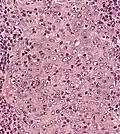

| Micrograph showing a nasopharyngeal carcinoma positive for Epstein-Barr virus-encoded small RNAs (EBER). | |

Nasopharyngeal carcinoma, also known as nasopharyngeal cancer, is classified as a malignant neoplasm, or cancer, arising from the mucosal epithelium of the nasopharynx, most often within the lateral nasopharyngeal recess or fossa of Rosenmüller (a recess behind the entrance of the eustachian tube opening). The World Health Organization classifies nasopharyngeal carcinoma in three types, in order of frequency: Non-keratinizing squamous cell carcinoma; keratinizing squamous cell carcinoma; and basaloid squamous cell carcinoma.[15] The tumor must show evidence of squamous differentiation; with the non-keratinizing type (also known as lymphoepithelioma), the tumor is most strongly associated with Epstein–Barr virus infection of the cancerous cells.[16]

Undifferentiated nasopharyngeal carcinoma—low power -

Undifferentiated nasopharyngeal carcinoma—med. power -

Undifferentiated nasopharyngeal carcinoma—high power -

Undifferentiated nasopharyngeal carcinoma—high power